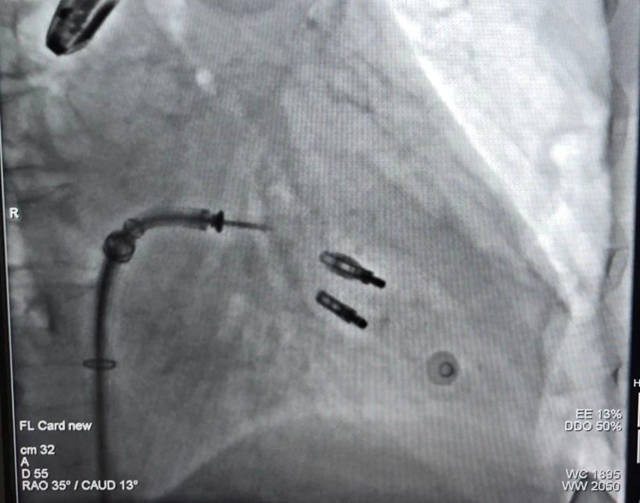

消毒、穿刺,手术正式开始。在超声影像科医生的食道探头指引下,一根1米多长的导管由股静脉缓慢放入,顺着血管逐步深入到心脏,抵达脱垂的瓣膜处。众人紧盯显示屏,看着两片瓣膜不断跳动。

“准备抓取。”夹子双臂缓缓张开。“闭合”罗钢教授看准时机,一声令下,夹子准确地夹住了瓣膜。那一刻,现场医护人员紧绷的心弦稍稍放松。

放了一枚夹子后,反流明显改善,但内侧仍存在对合不良的情况,医护人员刚放下的心又悬了起来。经评估,罗钢教授决定再放入第二枚夹子……

终于,历经2小时的紧张操作,两枚夹子准确夹住了张素芬重度脱垂的瓣膜,二尖瓣反流程度明显减轻。术后,张素芬恢复良好,胸闷、乏力等不适症状明显缓解,心脏功能指标得到显著改善。